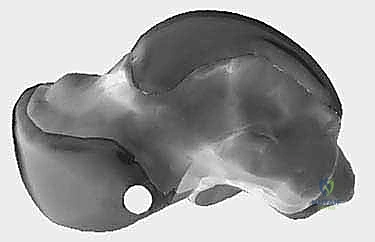

لفهم طبيعة مرض "إبهام القدم المتيبس"، يجب علينا أولاً إلقاء نظرة على التشريح الدقيق والمعقد لمفصل المشط السلامي الأول (1st MTP Joint). يتكون هذا المفصل من التقاء رأس عظمة المشط الأول (First Metatarsal) مع قاعدة السلامية الدانية (Proximal Phalanx) لإصبع القدم الكبير.

هذا المفصل ليس مجرد مفصل عادي؛ إنه يتحمل ما يقرب من 50% إلى 60% من وزن الجسم أثناء مرحلة الدفع (Push-off) في دورة المشي. لكي يعمل هذا المفصل بسلاسة، تغطى نهايات العظام بطبقة ناعمة ومرنة من الغضروف المفصلي (Articular Cartilage)، ويُحاط المفصل بكبسولة تحتوي على السائل الزليلي (Synovial Fluid) الذي يعمل كمشحم طبيعي.

عندما يبدأ الغضروف في التآكل بسبب الإجهاد المستمر أو الإصابات، تحتك العظام ببعضها البعض. كرد فعل طبيعي من الجسم لحماية المفصل من هذا الاحتكاك، يقوم بتكوين عظام جديدة على حواف المفصل تُعرف بالنتوءات العظمية (Bone Spurs). هذه النتوءات، التي تظهر عادة في الجزء العلوي (الظهري) من المفصل، تعمل كمصدات ميكانيكية تمنع الإصبع من الانثناء لأعلى، مما يؤدي إلى التيبس والألم الشديد.